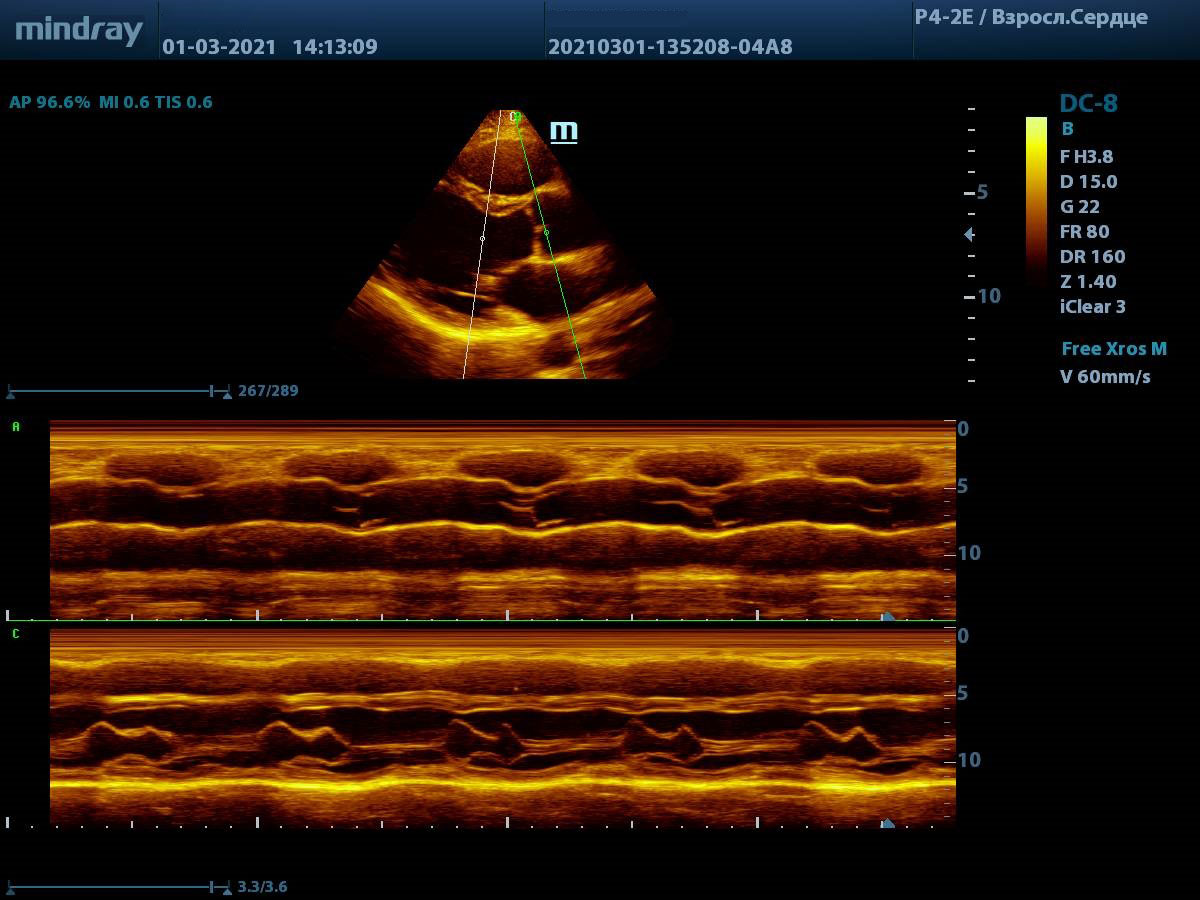

С М-режимом, первым из режимов эхокардиографии, знакомы все. Функцией свободного и анатомического М-режима активно пользуются обладатели машин высокого и экспертного класса. Эти функции используются для оценки створок митрального клапана, формы траектории их движения и амплитуды раскрытия, так же, как и для оценки синуса и полулуний аорты. Современные ультразвуковые диагностические системы компании Mindray, такой как экспертный прибор Mindray DC-8, способны проводить анализ в М-режиме сразу нескольких срезов до 3-х сечений за один раз. Больше не нужно отдельно выводить срез на уровне концов створок клапана и отдельно уровня синуса аорты. Всё получается нажатием пары кнопок и все готово к измерению.

Продвинутые операторы диагностической техники также владеют методами оценки функции желудочков в режиме Free Xros – свободном М-режиме. Такие параметры как TAPSE позволяют быстро и удобно оценить сократительную функцию правого желудочка, нормальное значение движения амплитуды кольца трикуспидального клапана 17 миллиметров или более.

Левый желудочек не остается в стороне, для него есть показатель MAPSE – измеряется в М-режиме и пересчитывается во фракцию выброса левого желудочка. Показатель более 10 мм считают нормой. Для расчета фракции необходимо подставить значение в формулу EF = 4.8 × MAPSE (mm) + 5.8. Такой способ оценки применяется только у взрослых. Использование нескольких срезов одновременно с функцией Free Xross позволит оценить сразу оба желудочка, что сильно экономит время и силы к концу трудового дня.